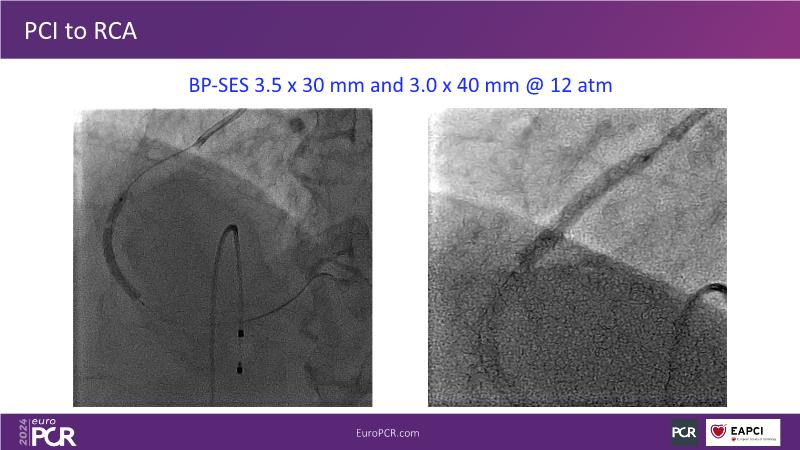

Tune into this 2024 session for insights into the latest ESC guidelines, strategies to prevent and treat no reflow, and an examination of trials like TASTE, TAPAS, and TOTAL on coronary thrombus management. Explore also the outcomes of the CHEETAH study, pondering a potential paradigm shift, and delve into a case study on thrombus removal in a patient with high thrombus burden.